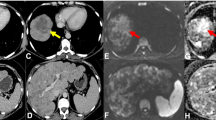

Changes in SULpeak and SUVmax were very closely correlated (r = 0.998). Consequently, the response classification (CR, PR, SD, or PD) was the same when SUVmax was used instead of SULpeak. Response categorizations as assessed by CE-CT and FDG PET/CT are summarized in Table 3. Overall, there was only fair to moderate agreement between response assessment by CE-CT and FDG PET/CT (kappa = 0.36, weighted kappa = 0.45). However, all 22 patients categorized as CR or PR by CE-CT were also categorized as CR or PR by PET/CT. In contrast, marked differences in response assessment were observed for the 43 patients categorized as SD or PD by CE-CT. Seventeen (40%) of these patients were classified as PR or CR by PET/CT (Table 3, Fig. 2). Of the 15 patients classified as PD by CE-CT, 3 were classified as CR by FDG PET/CT, 1 as SD, and 11 (73%) concordantly as PD. All three patients with discordant CR on PET/CT had new or progressive bone lesions on CE-CT. The 28 patients categorized as SD by CE-CT were classified by FDG PET/CT as CR in 6 cases, as PR in 8 cases, as PD in 6 cases (Fig. 3 ) and, concordantly, as SD in only 8 cases (29%). Of the 24 patients without osseous involvement, 9 (38%) had SD on CT and 2 (8%) had SD on PET/CT. Only two of the nine patients without osseous involvement and SD by CE-CT were also classified as SD by FDG PET/CT (one was categorized as CR, two were categorized as PR and four as PD; see Table 4 for details).

Eighty-six-year-old woman with metastatic breast cancer before and after first-line endocrine therapy combined with bevacizumab showing stable disease by CE-CT and complete response by PET/CT. CT images demonstrate several sclerotic foci in the spine, representing biopsy-proven osseous metastases (arrows in a), with no discernible change after treatment (c). Maximum-intensity projection PET/CT images show multiple FDG-avid metastases including the spine (short arrows), pelvis (dashed arrow), and ribs (dotted arrow) (b), with resolution after treatment initiation (d). Axial CT image of the pelvis in the same patient showing no metastases before (e) and after therapy (g). Corresponding axial PET/CT image showing multiple metastases before (f) and resolution of uptake after treatment (h). The patient is still alive with a follow-up of 47 months

Thirty-eight-year-old woman with metastatic breast cancer 10 days before (a, c, and e) and 80 days after (b, d, and f) initiation of desatanib and paclitaxel as first-line combination therapy showing stable disease by contrast-enhanced CT and progression by FDG PET/CT. Axial CT images before (a) and after (b) treatment initiation show stable axillary nodal metastases (arrow). Axial FDG PET/CT before (c) and after (d) treatment initiation show a marked increase in FDG avidity from an SULpeak of 2.1 to an SULpeak of 6.5. Mixed changes are seen on maximum-intensity projection PET images before (e) and after (f) treatment initiation. All nodes were stable on CT. The patient stayed on protocol as she did not meet criteria of progression by RECIST 1.1. Two months later, a new left axillary lymph node became palpable and the patient was switched to another treatment regimen

The marked differences in response classification by FDG PET/CT and CE-CT were often due to changes in the metabolic activity and number of osseous metastases (Fig. 2). Bone metastases can exhibit paradoxical behavior when responding to treatment with an increase in size and number of metastases, or the appearance of new lesions, because CT does not evaluate the bone marrow, but only the osteoblastic reaction in healing bone [16]. For this reason, RECIST 1.1 criteria specify that bone lesions without soft tissue components are non-measurable [4]. This limitation is problematic in patients with breast cancer because bone is often the dominant site of metastatic disease [17]. In contrast, FDG avidity reflects tumor viability, and can differentiate between tumor progression and healing bone [18, 19]. Additionally, FDG PET/CT is more sensitive than CT for the detection of osseous metastases [20]. Therefore, disease progression is detected earlier by FDG PET/CT than by CE-CT. While this principle advantage of metabolic imaging is well-known, to our knowledge, only a very limited number of studies have investigated the impact of better assessment of osseous disease on prediction of patient outcome [21].